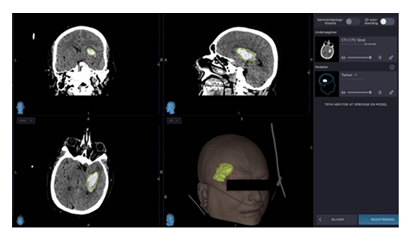

Variables

We reviewed the patients’ hospital notes for data on age, sex, body mass index (BMI), comorbidities, GCS at admission, alcohol intake, and smoking status. Data were measured on ICH localization, midline-shift (in mm), intraventricular extension, length, height, width, and volume measured by 3D-rending using a Medtronic Stealth device. An example of a 3D model is shown in figure 1.